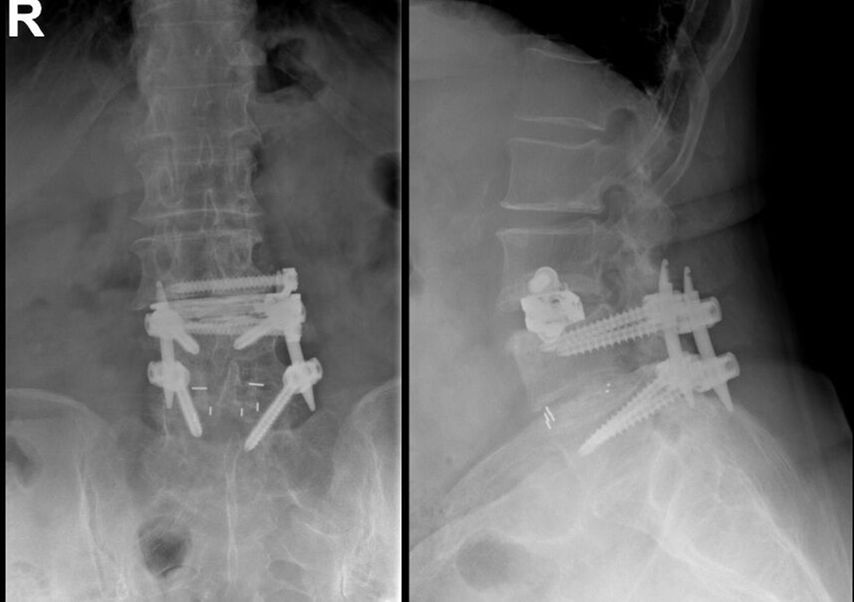

TLIF über Mittellinienzugang mit Schrauben in „cortical bone trajectory“. Bei der 63-jährigen Patientin bestand eine degenerative Spondylolisthese Meyerding Grad I mit Facettengelenkszysten und Wirbelkanalstenose (Abb. 8). Klinisch bestanden Lumboischialgien mit Ausstrahlung dem Dermatom L5 bds. entsprechend. Es wurde ein Mittellinienzugang durchgeführt und zuerst wurden navigierte Schrauben in „cortical bone trajectory“ platziert (Abb. 9). Anschließend erfolgten eine Facettektomie L4/5 links und eine Dekompression des Wirbelkanals. Abbildung 10 zeigt, dass der Hautschnitt aufgrund der mittelliniennahen Schraubenköpfe klein gehalten werden kann. Klinisch wurden die lumbalen Schmerzen wie ausstrahlende Beschwerden 1 Jahr postoperativ annähernd vollständig behoben, die korrespondierende Röntgenkontrolle ist in Abbildung 11 dargestellt.